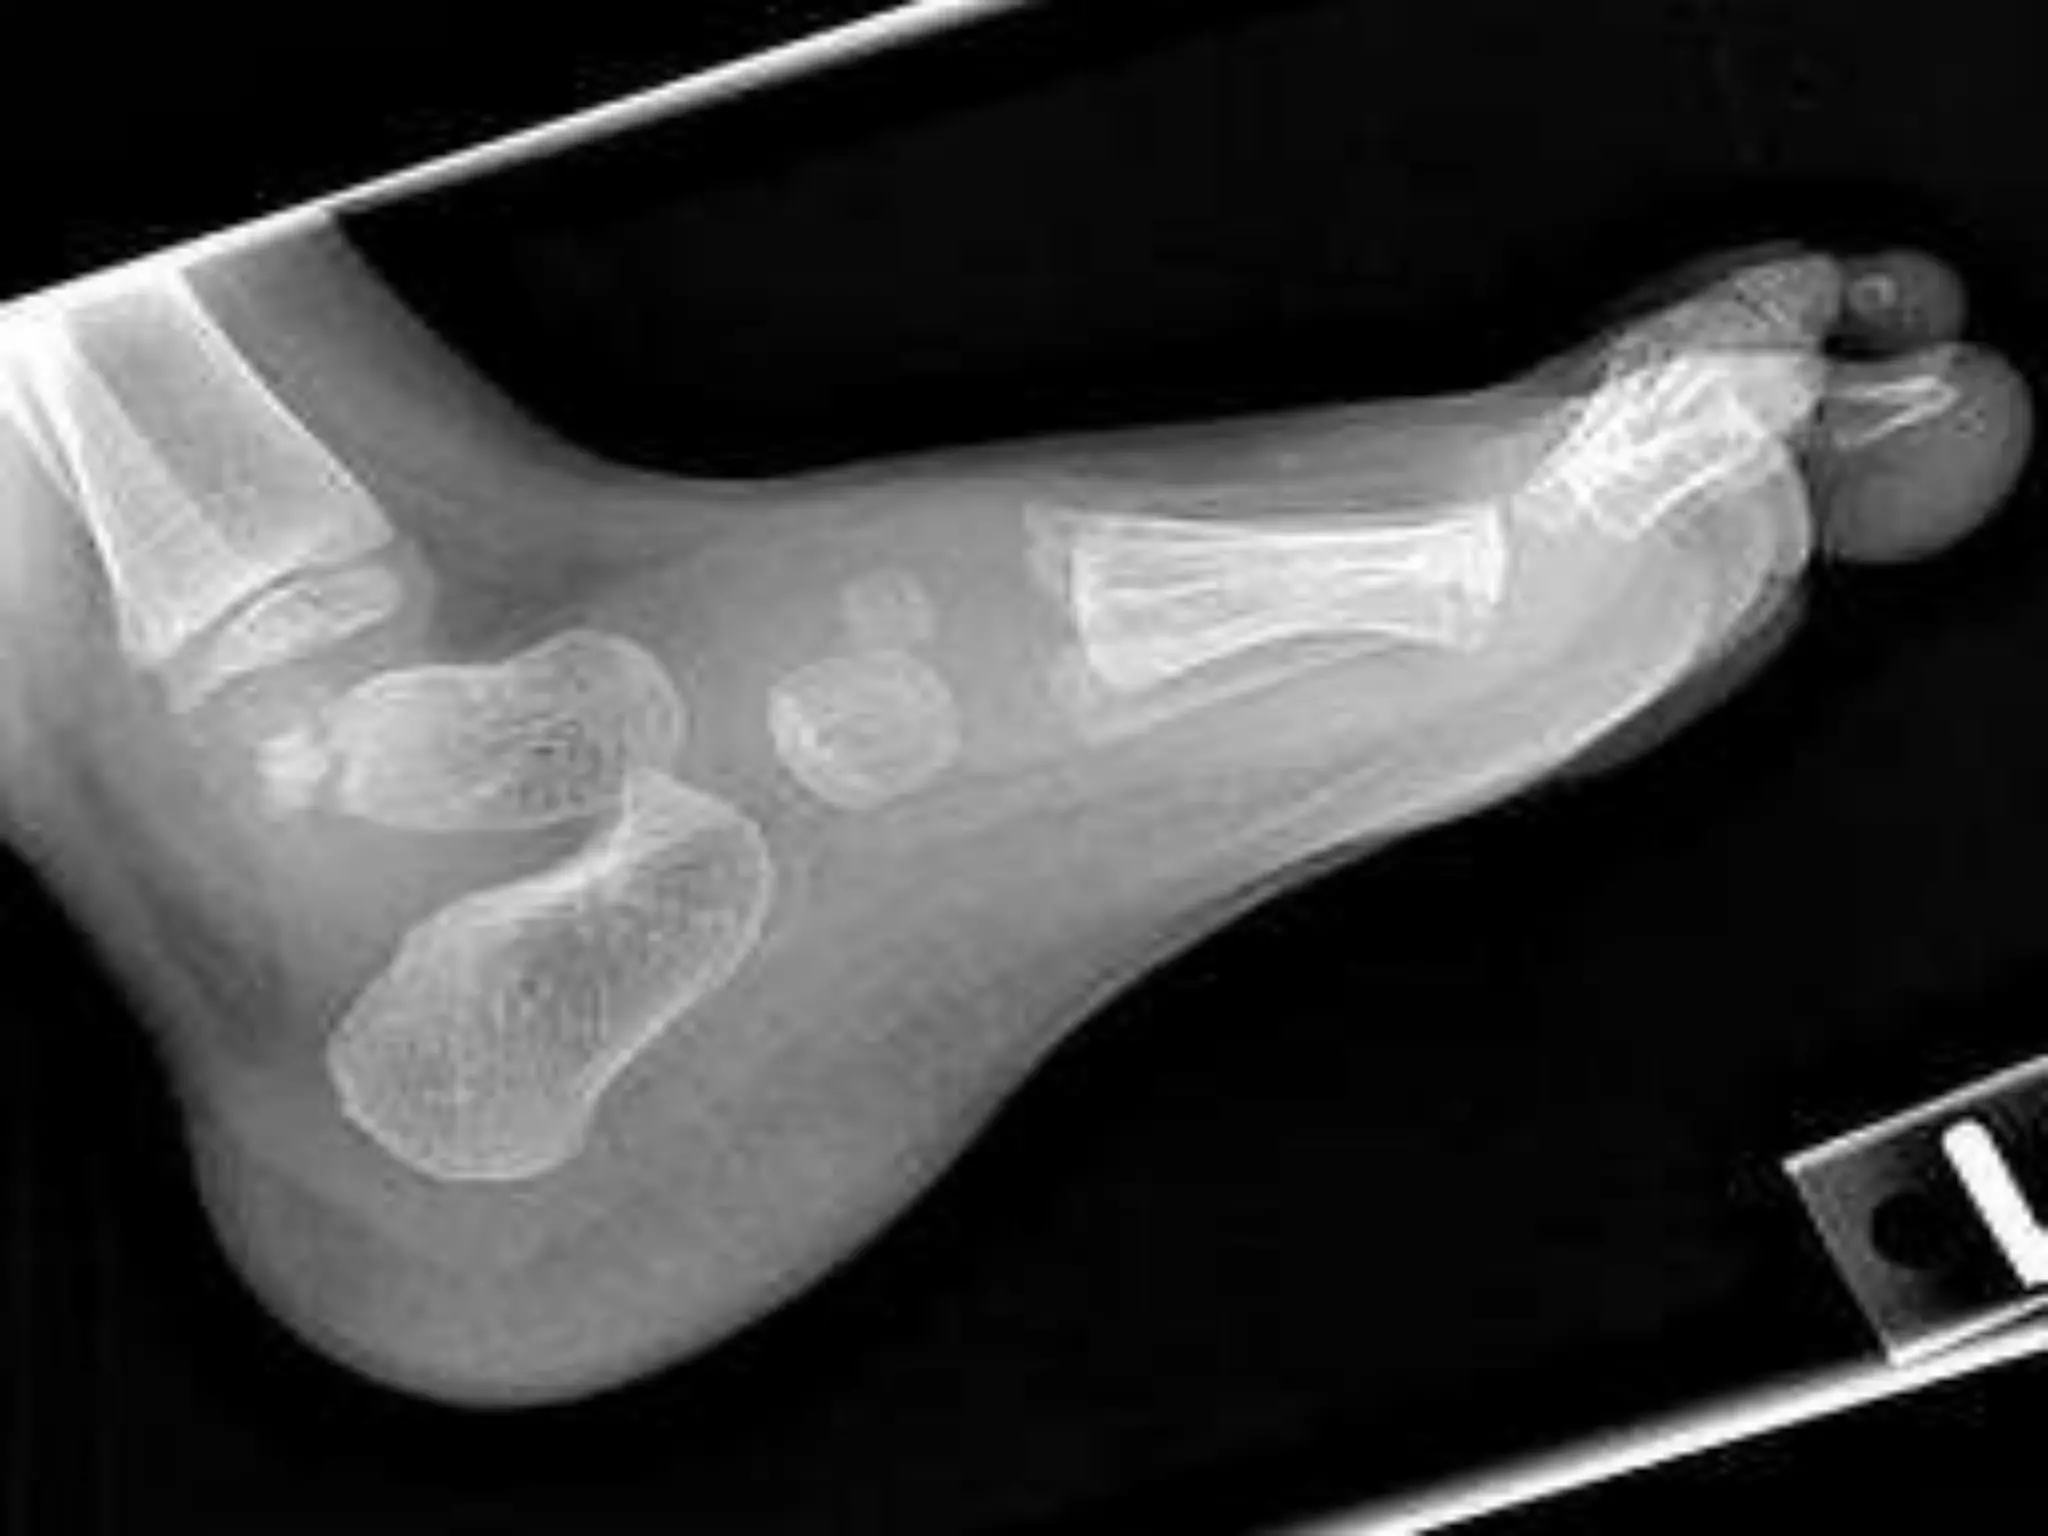

Mafucci’s syndrome(rare)

characterised by multiple

enchondromas.

Soft tissue

haemangiomas

(skin/viscera).

Malignant changes in

soft tissue and bone

lesions.

Mafucci’s syndrome(rare) characterised bymultiple enchondromas. Soft tissue haemangiomas (skin/viscera). Malignant changes in soft tissue and bone lesions.